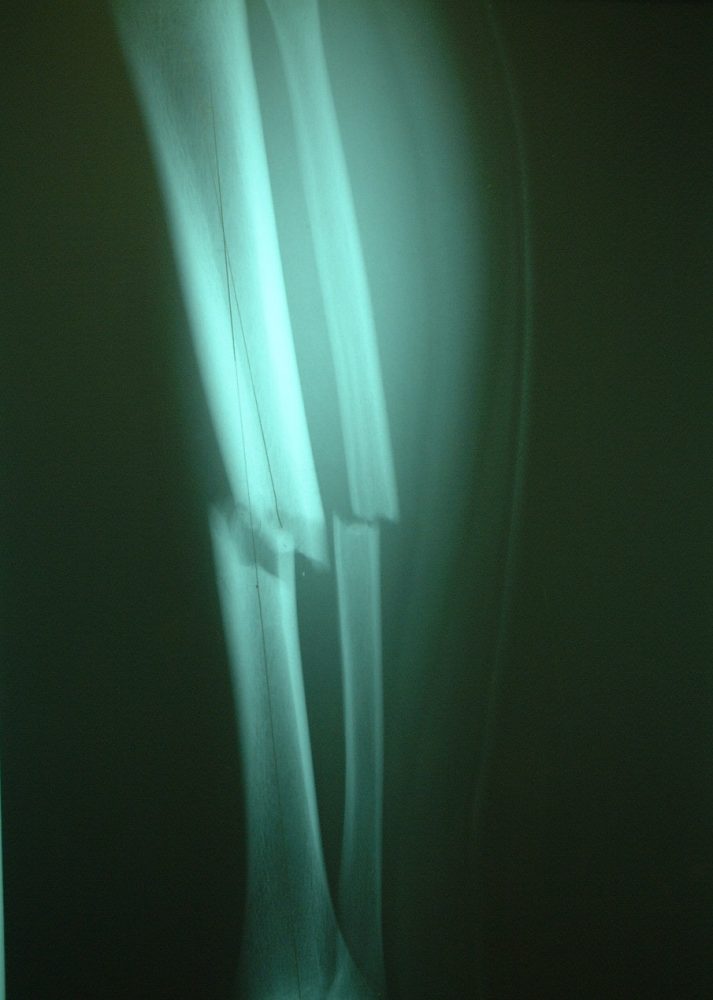

Photo 2 is an X-ray image of the same case as Photo 1. The tibia and fibula are shown in lateral view with a spiral fracture at the diaphysis, but the ankle is rotated 90 degrees and facing anteriorly.